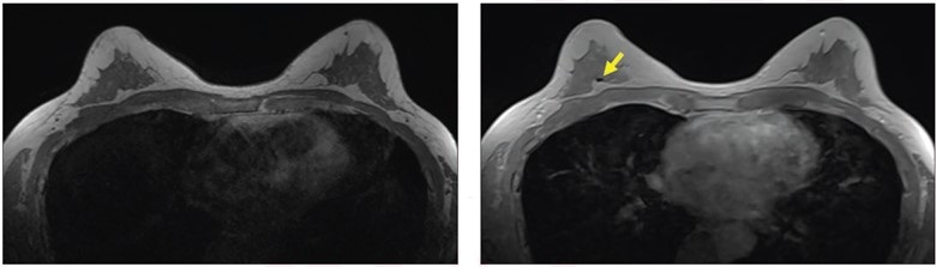

57-year-old patient with breast biopsy clips who underwent breast MRI for high-risk screening. A. Axial T1-weighted non-fat-saturated MR image shows no area of signal void. No reader detected clip using this sequence. B. Axial contrast-enhanced in-phase Dixon image shows signal void in right breast (arrow), which corresponded with MammoMark/CorMark Bread Tie biopsy clip. All three readers detected clip on this sequence, with confidence scores of 4, 3, and 2; assessments all classified as true positives (i.e., detected with confidence score ≥2).

“Compared with clinical sequences, contrast-enhanced in-phase Dixon had higher sensitivity for detecting breast biopsy clips on MRI, as well as higher reader confidence and contrast-to-noise ratio (CNR), without change in positive predictive value (PPV),” wrote corresponding and co-first author, Michael W. Taylor-Cho, MD, MPH, of Duke University Medical Center in Durham, NC.

Ultimately, compared with T1W NSF, STIR, and T1WFS sequences, the contrast-enhanced in-phase Dixon sequence evidenced the highest sensitivity for breast biopsy clip detection (85.1% vs. 26.6%-78.2%), highest reader confidence (3.5 vs. 1.7–3.0), and highest CNR (4.05 vs 0.54–1.21), without a significant difference in PPV (96.4% vs. 92.2%–96.1%).